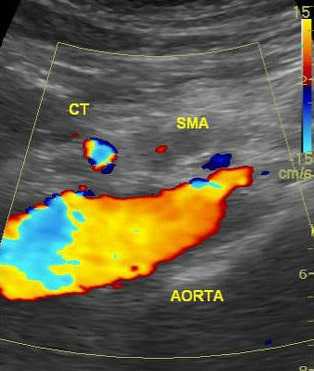

6. УЗДГ (чувствительность 80%). Метод особенно эффективен при подозрении на стеноз нескольких сосудов.

Высокую прогностическую ценность имеют отклонения от нормы пиковой систолической скорости кровотока (S), которая ориентировочно составляет более 275 см/с для ВБА или 200 см/с для НБА (по некоторым данным > 300 см/с).

Нормальная скорость после приема пищи должна увеличиться примерно на 20% и более.

Ненормальный постпрандиальный ответ интерпретируется как увеличение пиковой систолической скорости менее чем на 20%.

Тяжелым считает стеноз артерий, составляющий более чем 60-70%, который выявляется при триплексном сканировании. При этом на допплерограмме ниже места поражения ламинарный поток исчезает и появляется турбулентный поток.

Неинвазивное дуплексное ультразвуковое сканирование дает важную информацию о физиологии чревного ствола и ВБА. Если планируется операция или результат дуплексного сканирования сомнителен (см. обсуждение), выполняют ангиографию. Наиболее информативным является боковой снимок.

26. Когда лучше для диагностики хронической мезентериальной ишемии выполнять дуплексное УЗИ — натощак или после еды?

Если пик скорости кровотока в систолу натощак превышает 275 см/сек, то соответствующая артерия стенозирована на 70% или более. В таких случаях чувствительность составляет 89%, а специфичность — 92%. До сих пор врачи не пришли к однозначному заключению, следует ли определять скорость кровотока после приема пищи у больных, если у них во время исследования натощак уже получены данные, говорящие об окклюзии (> 275 см/сек).

Результат исследования после еды считают положительным, если после пищевой нагрузки наибольшая систолическая скорость увеличилась менее чем на 20%. Диагностическая ценность исследования после еды представляется минимальной.